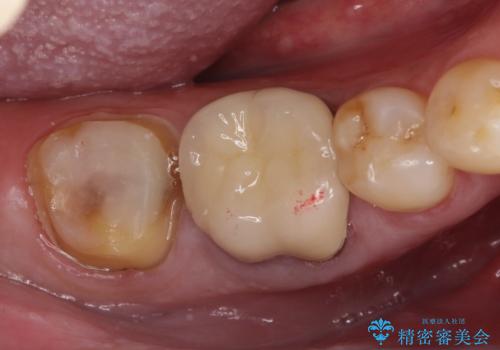

- 奥歯の詰め物が取れたことを主訴に来院されました。

噛む力が非常に強いため、破折しづらいゴールドクラウンにて修復治療を行なっています。

咬合力の強い患者さんに対してはセラミッククラウンでは破折リスクが高いためゴールドクラウンが適しています。